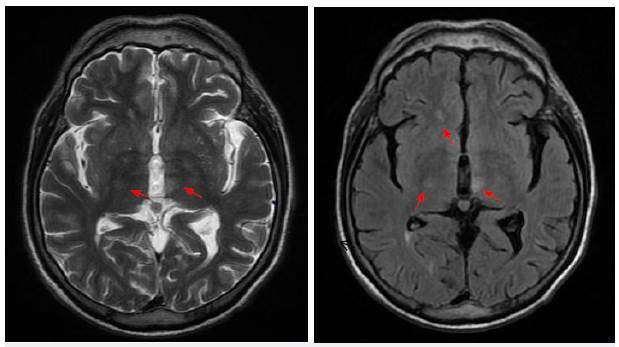

La resonancia magnética de neuroeje evidenció lesión hiperintensa centromedular C3-C7 y torácica T2-T5 Y T7-T10. La imagen cerebral muestra lesión hiperintensa en T2 y FLAIR en tálamo medial izquierdo (figuras 1, 2 y 3).

Figura 1 Corte axial en T2 con lesiones talámicas bilaterales hiperintensas (flechas), el aumento de señal en FLAIR sugiere gliosis (cabeza de flecha). Imagen propia del caso (Clínica La Misericordia).